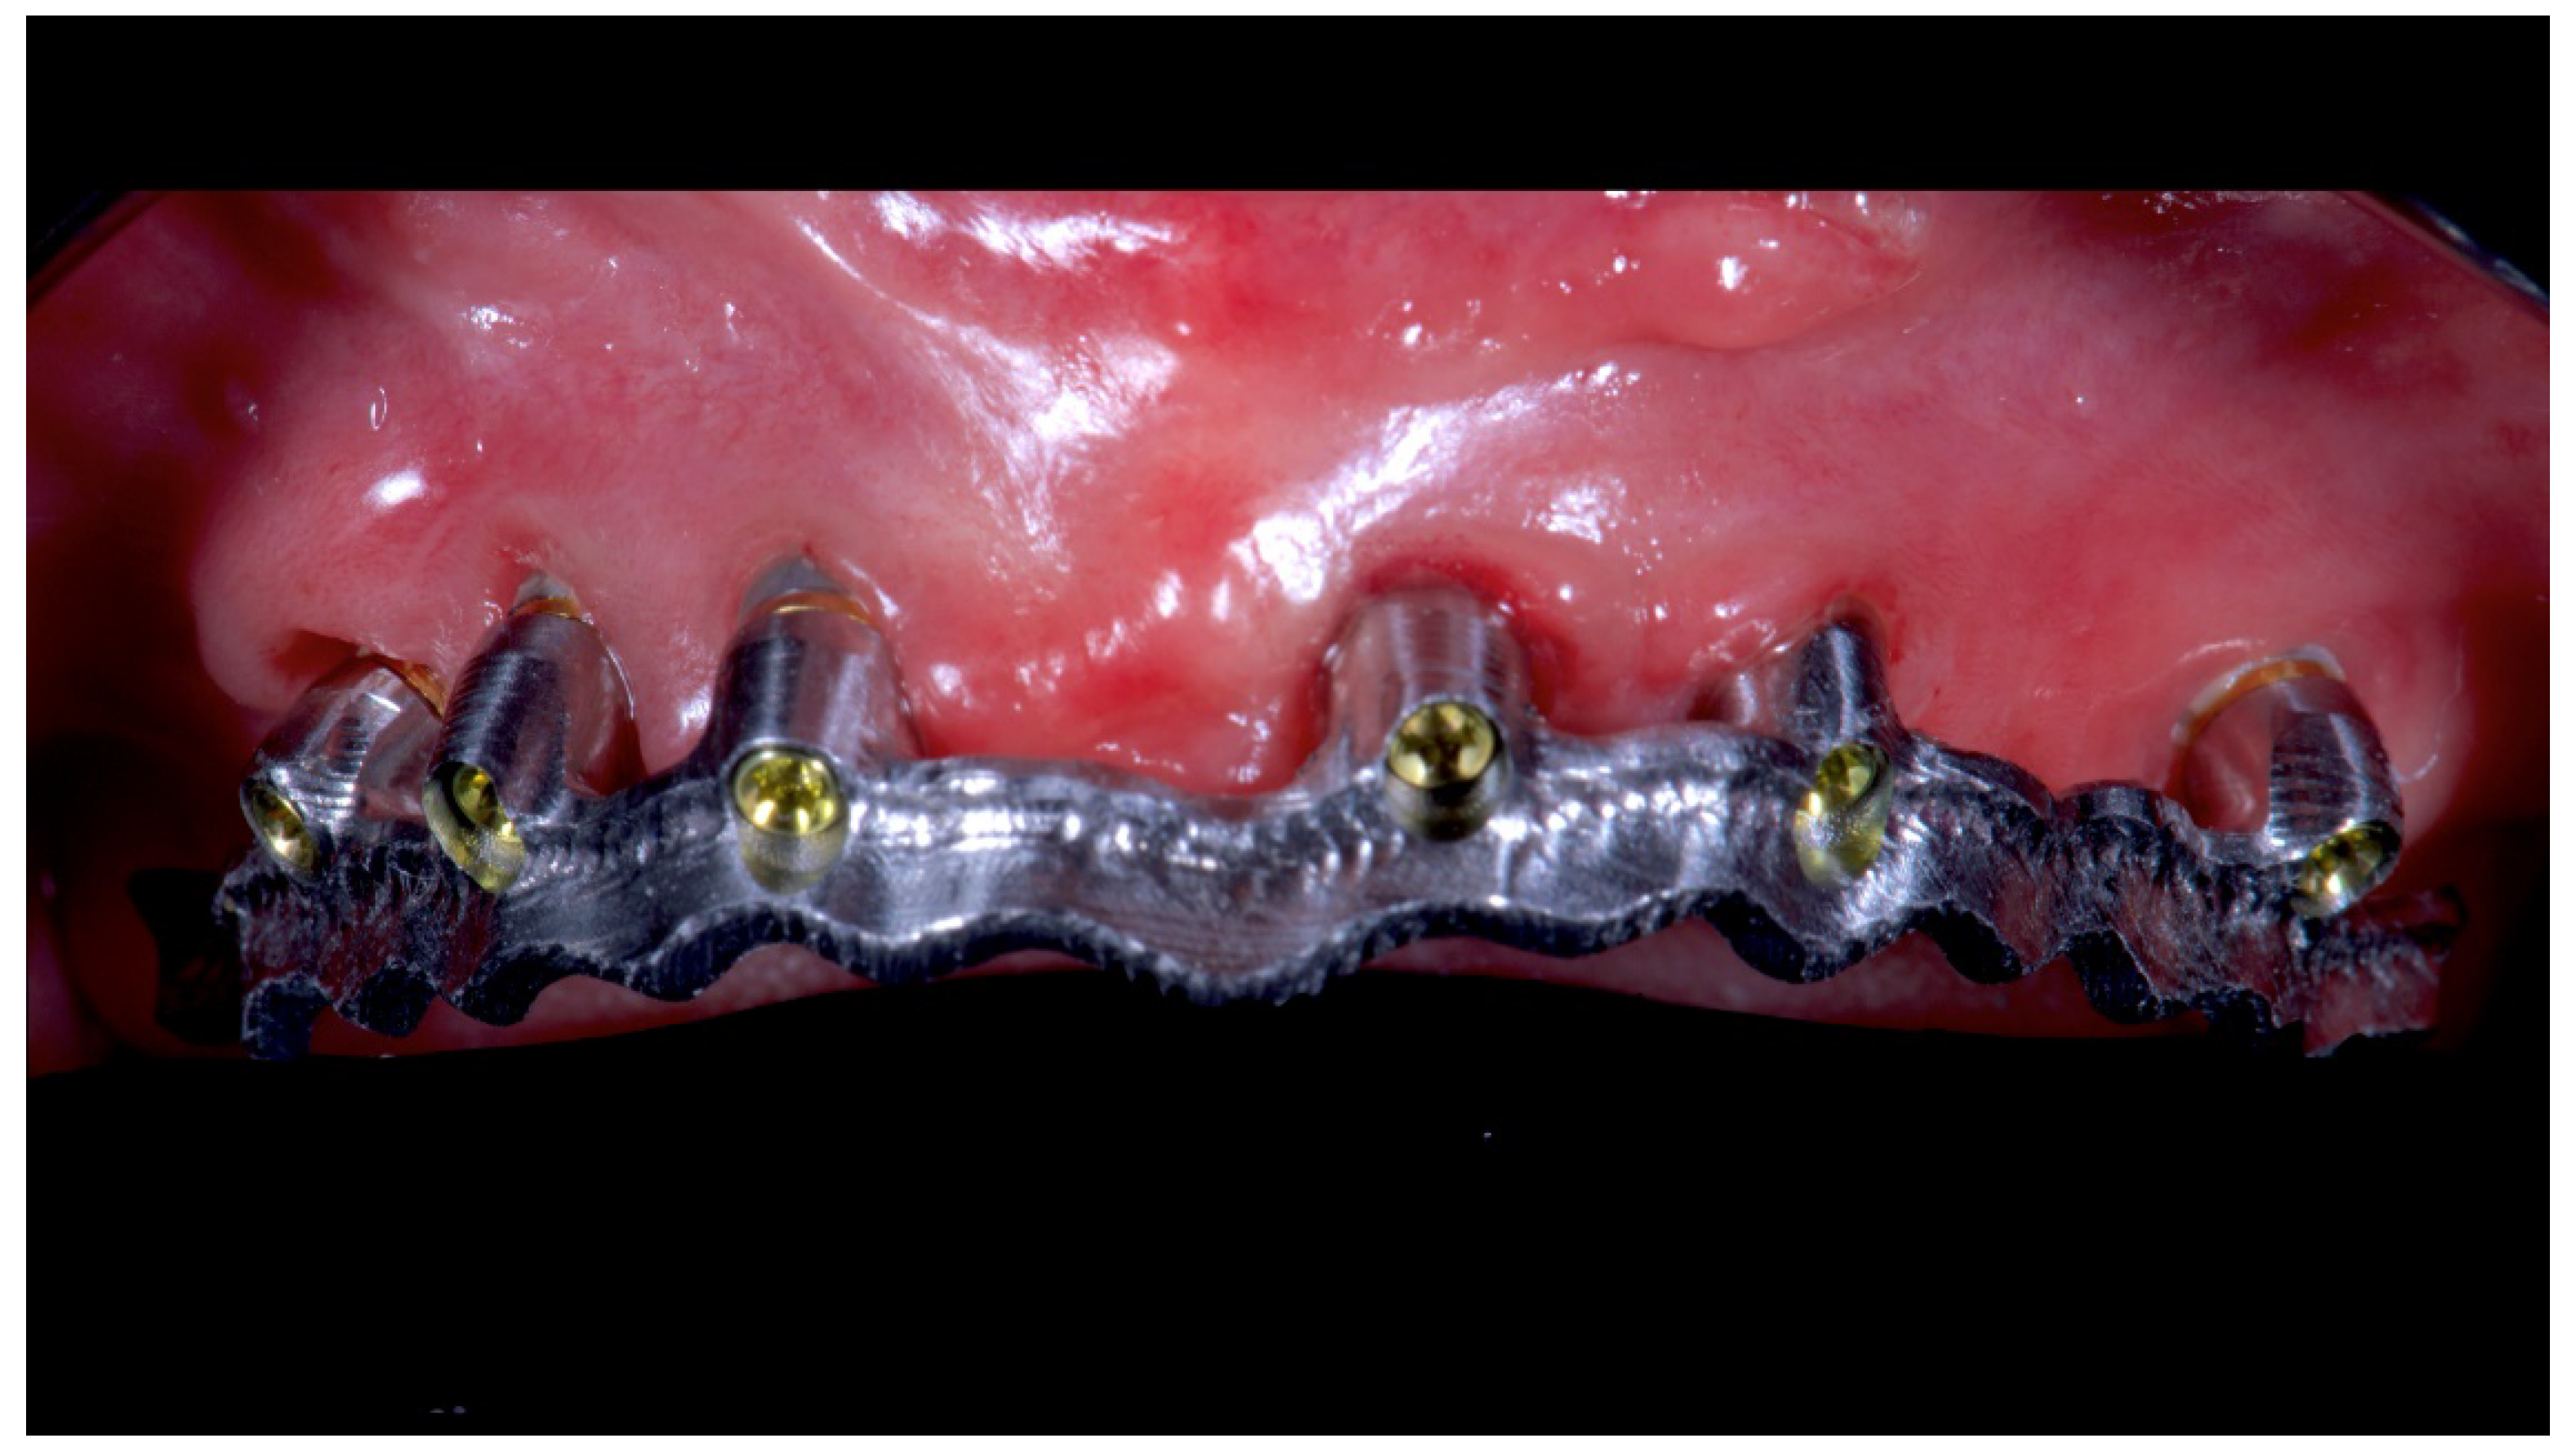

Figure 12.

Single frame titanium bar mounted in maxillae with OT Bridge system.